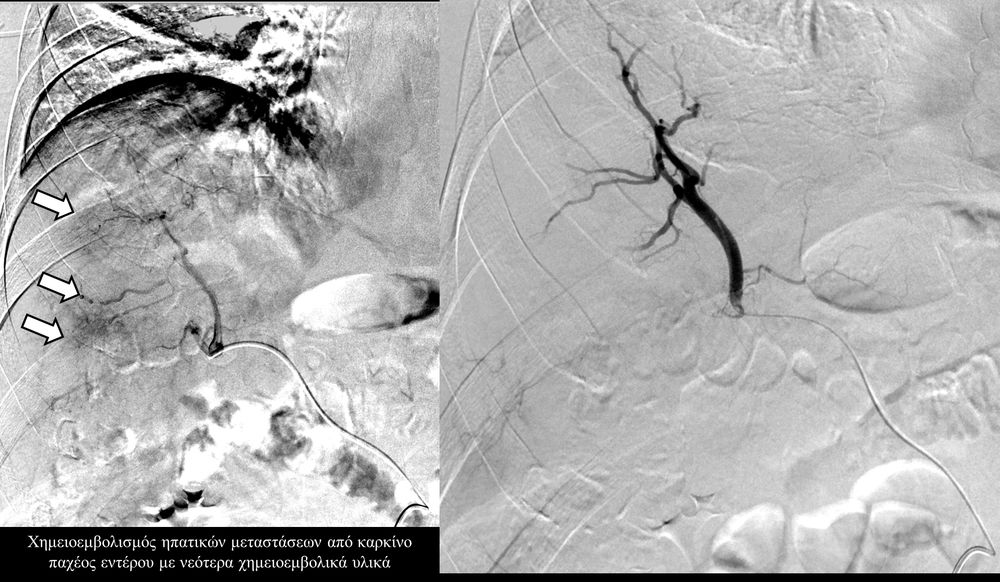

Ο χημειοεμβολισμός είναι μέθοδος τοπικής χημειοθεραπείας για πρωτοπαθή και δευτεροπαθή νεοπλάσματα του ήπατος. Σκοπός του είναι η τοπική έγχυση χημειοθεραπευτικού σε κλάδους της ηπατικής αρτηρίας, ώστε να επιτευχθούν υψηλές συγκεντρώσεις τοπικά στην ηπατική εξεργασία χωρίς να προκαλούνται οι συστηματικές επιπλοκές τοξικότητας του χημειοθεραπευτικού. Επιπλέον προκαλείται τοπική ισχαιμία στην περιοχή του όγκου από τα εμβολικά υλικά-μικροσφαιρίδια εμβολισμού.

Ενδείκνυται επίσης σε ηπατικές μεταστάσεις από νευροενδοκρινείς όγκους, καρκίνο παχέος εντέρου και μελάνωμα, σε συνδυασμό με συστηματική χημειοθεραπεία της οποίας ενισχύει και βελτιώνει τα αποτελέσματα.